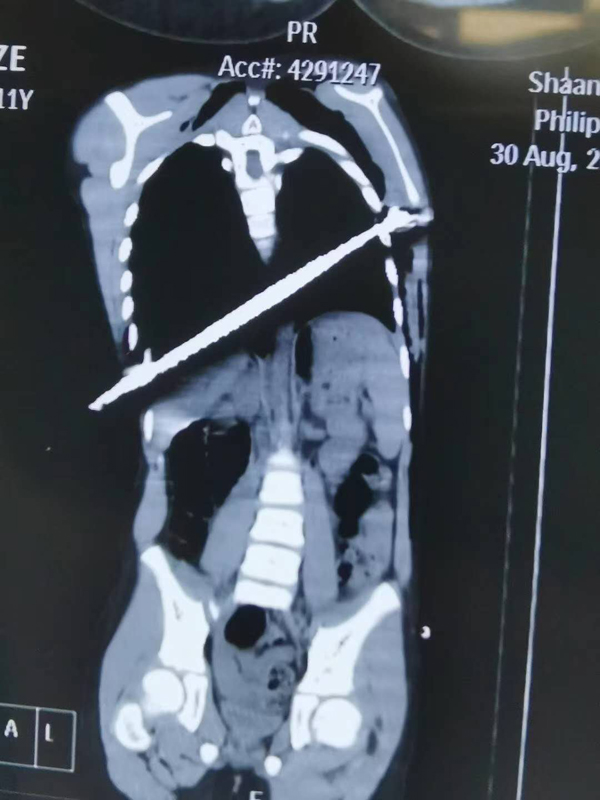

8月30日晚上8点左右,陕健医二一五医院胸外科的值班医生郭小琦接到紧急通知,一位11岁的男童在玩耍时不慎被钢筋刺伤右侧胸部,贯穿左右胸腔,正在紧急转来的途中。郭医生立即赶到急诊科,发现患儿被钢筋刺入右侧胸壁外露10余cm长,失血较多,剧烈疼痛,表情痛苦,情况万分危急。郭医生一边打电话向科主任薛锋报告,一边与手麻科医生联系,同时开通绿色通道,迅速准备好抢救设备,紧急行胸部CT,并通知手术室、麻醉科做好急诊手术的准备。

薛锋主任很快赶到科室,了解患者伤情,为手术做准备。因尚不确定钢筋是否损伤到心脏和主动脉,手术存在很大的难度与风险,胸外科手术医生团队迅速探讨手术方案,给出各种可能出现的紧急情况的补救措施,制定出手术方案和应急预案。

各项术前准备工作极速完成后,约晚上10点,胸外科手术团队及手麻科团队,在急诊全麻下经胸腔镜辅助下双侧胸腔探查、双侧肺贯通伤修补、双侧血胸清楚、肋间血管缝扎止血、胸腔异物取除、胸壁伤口扩创缝合术,在胸外科与手麻科的共同协作下,经过约4个多小时的不懈努力,在确保重要脏器无损伤的情况下,安全拔除长约40cm钢筋,手术顺利结束,风险解除。所有医生和家属悬着的心终于落下。